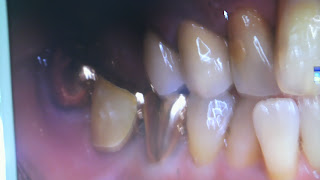

この写真はインプラントをした方の写真です☆

下の奥歯3本歯が無かったのですが,インプラントを入れたので自分の歯のように入りました!!

インプラントをした方達は快適なようで,こちらもとても嬉しいですo(^-^)o